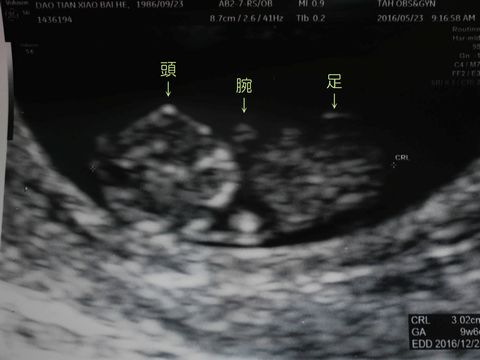

超音波の検査では、3週間前はまったく何の形がわからなかった胎児が、今回は赤ちゃんの形らしきものに